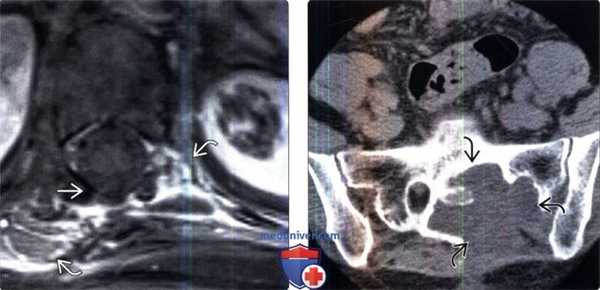

(Слева) Сагиттальный КТ-срез: признаки деструктивного процесса В, распространяющегося из спинномозгового канала в крестец.

(Справа) Сагиттальный срез, Т1-ВИ с КУ, этот же пациент: активно и неоднородно накапливающая контраст ГПЦ- подобная опухоль, заполняющая собой нижние отделы спинномозгового канала пояснично-крестцового отдела позвоночника и прорастающая в тело крестца.

(Слева) Аксиальный КТ-срез: ярко контрастирующееся четко ограниченное объемное образование дорзальных мягких тканей на уровне верхнешейного отдела позвоночника.

(Справа) На цифровой субтракционной ангиограмме в боковой проекции этого же пациента визуализируется гиперваскуляризированная опухоль, представляющая собой гемангиоперицитому.